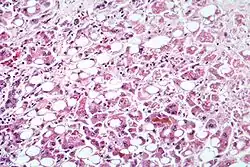

Alcoholic hepatitis as seen with a microscope, showing fatty changes (white circles), remnants of dead liver cells, and Mallory bodies (twisted-rope shaped inclusions within some liver cells). (H&E stain)

Steatohepatitis is seen in both alcoholic and non-alcoholic liver disease and is the culmination of a cascade of events that began with injury. In the case of non-alcoholic steatohepatitis, this cascade is initiated by changes in metabolism associated with obesity, insulin resistance, and lipid dysregulation.[66][67] In alcoholic hepatitis, chronic excess alcohol use is the culprit.[68] Though the inciting event may differ, the progression of events is similar and begins with accumulation of free fatty acids (FFA) and their breakdown products in the liver cells in a process called steatosis.[66][67][68] This initially reversible process overwhelms the hepatocyte's ability to maintain lipid homeostasis leading to a toxic effect as fat molecules accumulate and are broken down in the setting of an oxidative stress response.[66][67][68] Over time, this abnormal lipid deposition triggers the immune system via toll-like receptor 4 (TLR4) resulting in the production of inflammatory cytokines such as TNF that cause liver cell injury and death.[66][67][68] These events mark the transition to steatohepatitis and in the setting of chronic injury, fibrosis eventually develops setting up events that lead to cirrhosis and hepatocellular carcinoma.[66] Microscopically, changes that can be seen include steatosis with large and swollen hepatocytes (ballooning), evidence of cellular injury and cell death (apoptosis, necrosis), evidence of inflammation in particular in zone 3 of the liver, variable degrees of fibrosis and Mallory bodies.[66][69][70]

Liver biopsies show identical findings in patients with ASH and NASH, specifically, the presence of polymorphonuclear infiltration, hepatocyte necrosis and apoptosis in the form of ballooning degeneration, Mallory bodies, and fibrosis around veins and sinuses.[34]